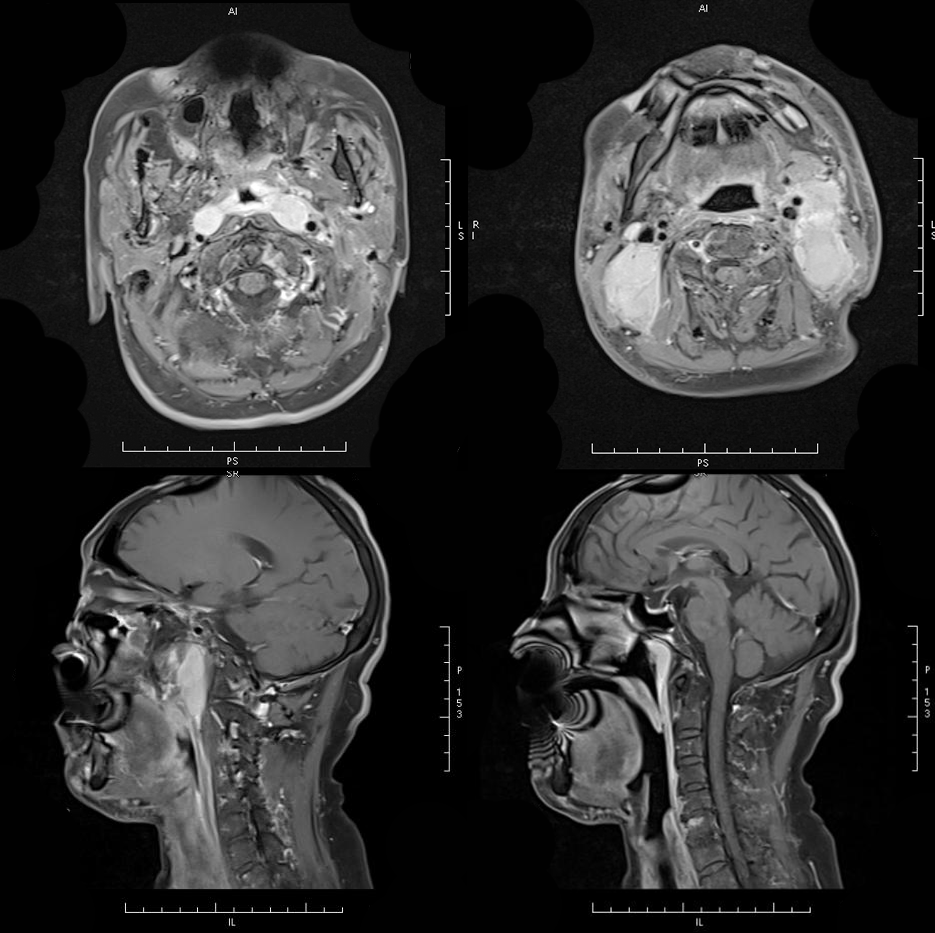

MRI 表现:鼻咽后壁及两侧壁不规则软组织肿块,信号多较均匀,T1WI 像呈等信号,T2WI 像呈稍高信号,DWI 像为明显高信号。增强扫描肿块常轻-中度均匀强化,液化坏死少见。颈部淋巴结肿大常见。肿大淋巴结多边缘规则,内部密度或信号均匀,增强扫描轻度强化。对邻近组织侵犯少,肿块与咽后壁头长肌等分界清楚,多无颅底及相邻骨质破坏。鼻咽部肿块虽较明显,但咽旁间隙较清晰,或只有受压改变。

MRI 表现:早期表现为鼻咽顶后壁轻度软组织增厚、突起,表面不规则、边界不清;咽隐窝变浅甚至消失,鼻咽轮廓改变,双侧结构不对称;进展期肿瘤增大向周围组织、结构浸润生长,并可破坏颅底骨质结构,以中线部蝶骨体和枕骨斜坡最常见。肿瘤在 T1WI 像上呈中等或中低信号,T2WI 像上呈中等或中高信号,边缘模糊呈浸润状;增强扫描多呈明显强化,肿块内坏死区无强化。颈部较小的转移淋巴结边缘多较清楚、信号均匀;较大的淋巴结中央常见液化坏死,多发增大的淋巴结可融合呈巨大的肿块,信号不均匀。